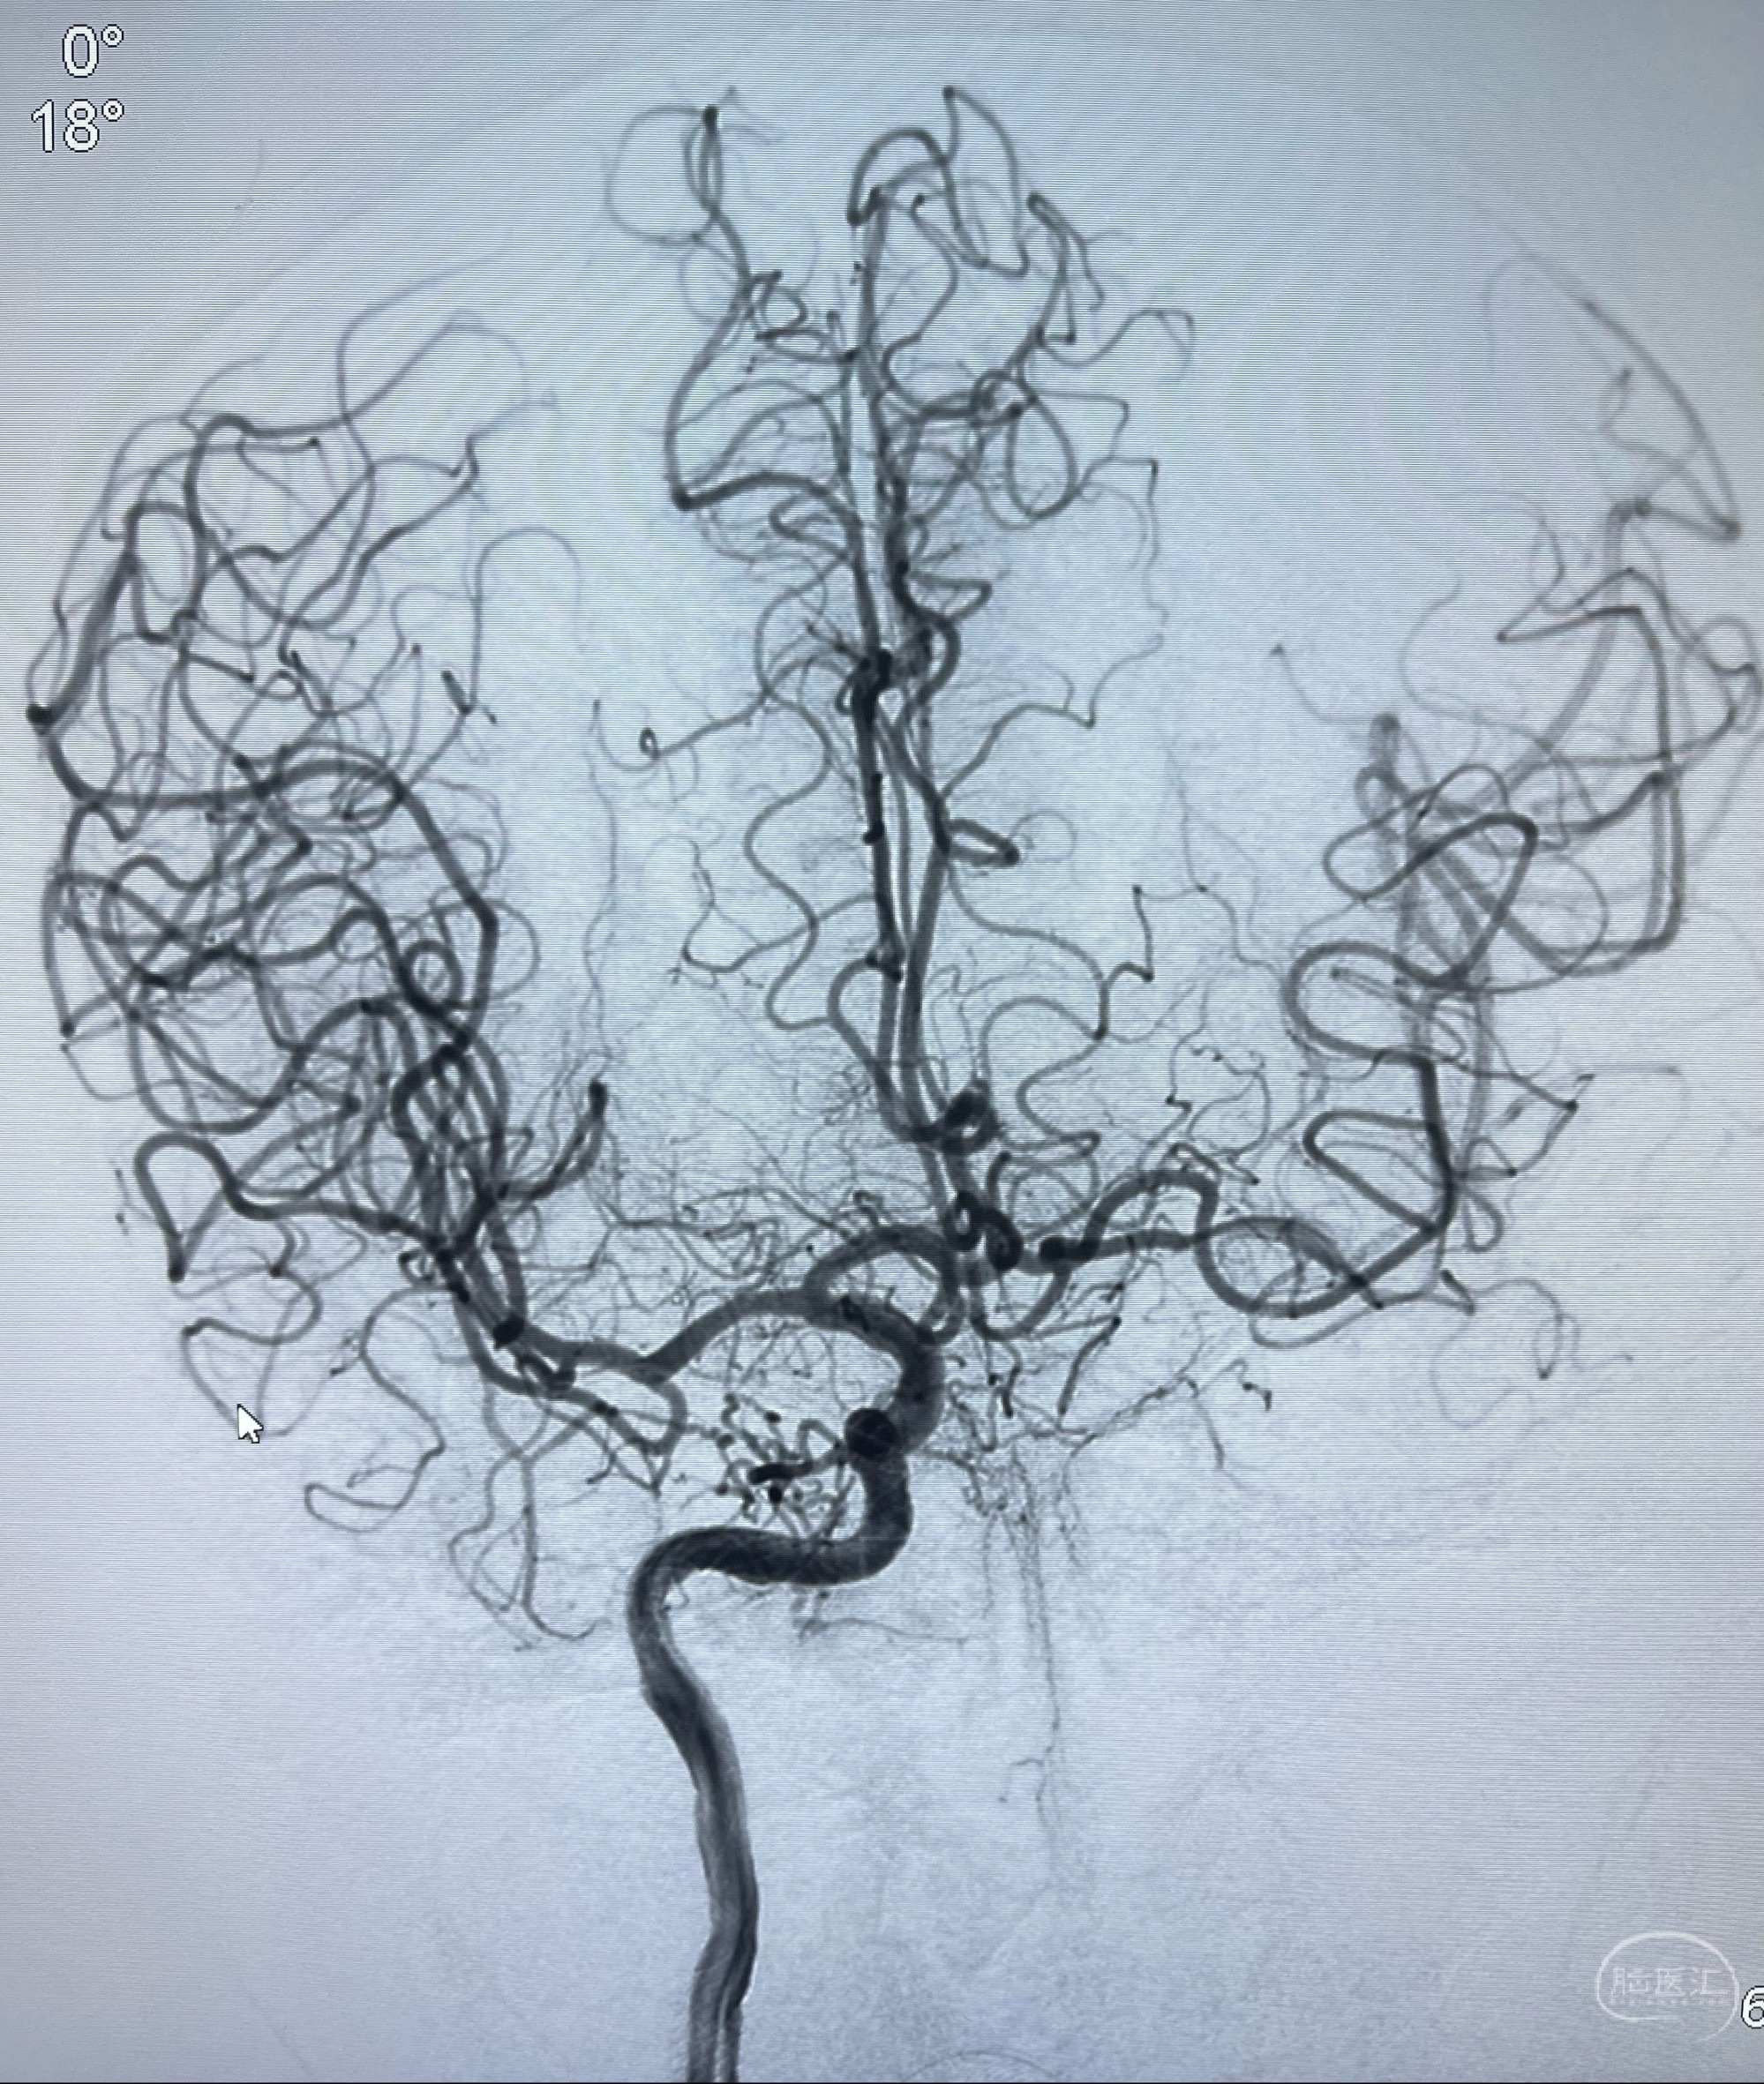

2023-07-10DSA:右侧颈内动脉岩骨段夹层伴中偏重度狭窄改变,左侧颈总动脉闭塞、右侧颈外动脉由右侧肋颈干甲颈干吻合代偿

右侧椎动脉可见吻合代偿右侧颈外动脉

左侧颈总动脉起始段至分叉部闭塞,起始部呈现子弹头样改变

左侧椎动脉可见代偿显示左侧前循环